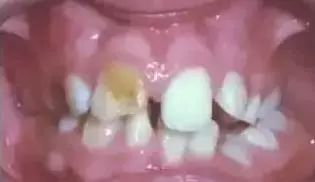

然而并没有好好地护理,乳牙蛀了,刚开始是这样的

老人说,乳牙要换的,不用补。然后就变成这样了

釉质发育不全